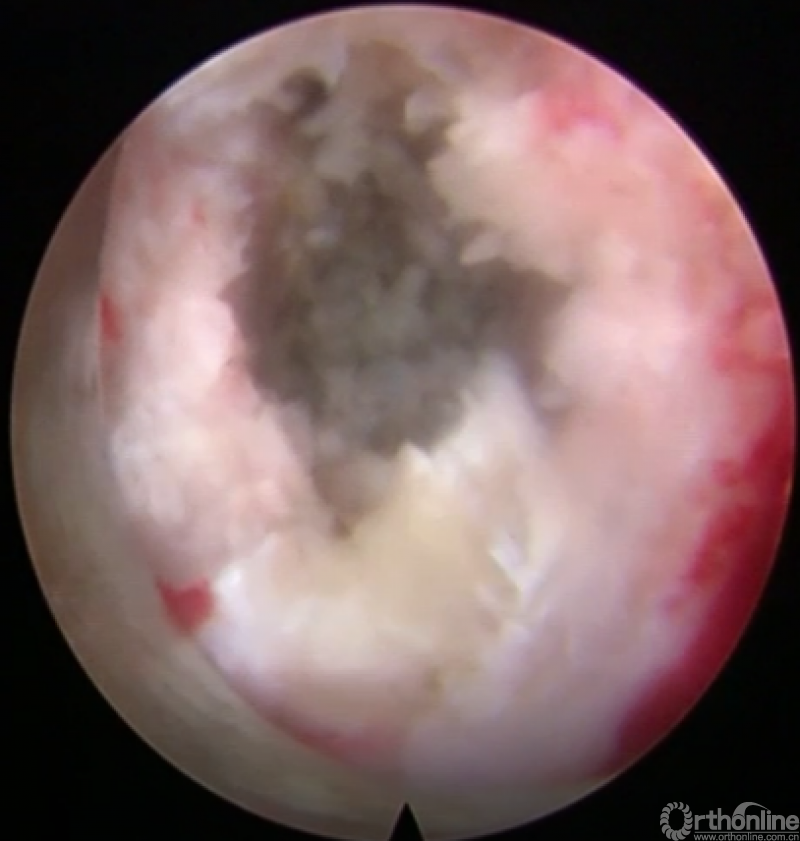

第九步“填”;椎间隙填塞植骨;

第十步“置”:置入融合器、经皮钉。